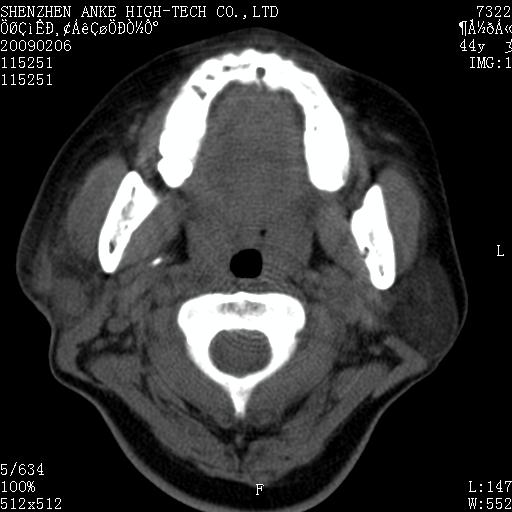

标题: CT17977:女,44岁,右侧颌部包块1年,右侧面瘫2月。 [打印本页]

患者:女,44岁,右侧颌部包块1年,右侧面瘫2月。

考虑右侧腮腺混合瘤可能性大

考虑右侧腮腺混合瘤。

考虑右侧腮腺混合瘤。年轮样伪影考虑机器问题!

右侧腮腺混合瘤可能性大

考虑右侧腮腺混合瘤;不排除腮腺癌。

右侧腮腺肿瘤,良恶性难定。

右侧腮腺混合瘤。机器没有调试好。